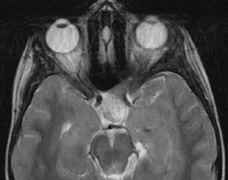

1. Schwannomas most commonly affect the fifth cranial nerve (CN), but any cranial nerve may be affected. In contrast to vestibular schwannomas (CN VIII), these typically do not grow large.84,90 Vestibular schwannomas (acoustic neuromas) are the classic finding in NF2 (Fig. 7). The risk for malignant transformation is low, but may be higher with radiation exposure.84,94

3. Other tumors: low-grade ependymomas and gliomas may affect the cervical spine and Brainstem (Fig. 7).84

Fig. 7. Neurofibromatosis type 2: Images of a 12-year-old boy with deafness and weakness in his arms and legs, whose father has bilateral deafness. Axial T2-weighted (a) and postcontrast axial (b) T2-weighted images reveal bilateral vestibular schwannomas, which are also known as acoustic neuromas (arrows). This is the classic finding of NF2. (b, c) Bilateral schwannomas are seen in Meckel's cave (arrowheads) and a (d) lower left cranial nerve schwannoma extends into the pars nervosa of the jugular foramen (arrow). (e) A part cystic and part solid enhancing ependymoma in seen within the cervical cord and medulla and within the distal cord and conus. (e, f) Thoracic schwannomas are present at numerous levels (arrowheads). Marked enhancement and thickening of the roots within the cauda equina also represent multiple schwannomas.